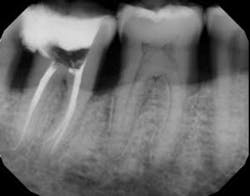

Each instrument and its accompanying technique have their own advantages and disadvantages. The key is to find a system to use in which all of the components are made to work together synergistically, such that they result in a procedure that is easy for the dentist to achieve the desired end results. In this instance, the desired end result is a debrided, clean canal that has been enlarged, shaped, and finished to receive a gutta-percha and sealed obturation (figures 1–4). This should be able to be achieved in an easy, quick, not too expensive, predictable, operator friendly manner. The dentist should not have to be Michelangelo to achieve the desired result consistently on every patient.

Next, the 30/.04 NiTi (two blue bands) instrument is used to create the final .04 taper in the canal (figure 6). This instrument will also be several millimeters short at first. I take between four and eight pecks to achieve the working length. Trying to push the instrument to measurement will just slow down the procedure and not accomplish the goal. The more you peck with it, the faster you will achieve the working length. Copious irrigation should be used, because these instruments cut very well and produce a lot of dentinal dust. Once the finisher is used, we now have prepared the canal to a 30 at the apex with a .04 taper. Included in the introductory kit is box of precision gutta-percha points.